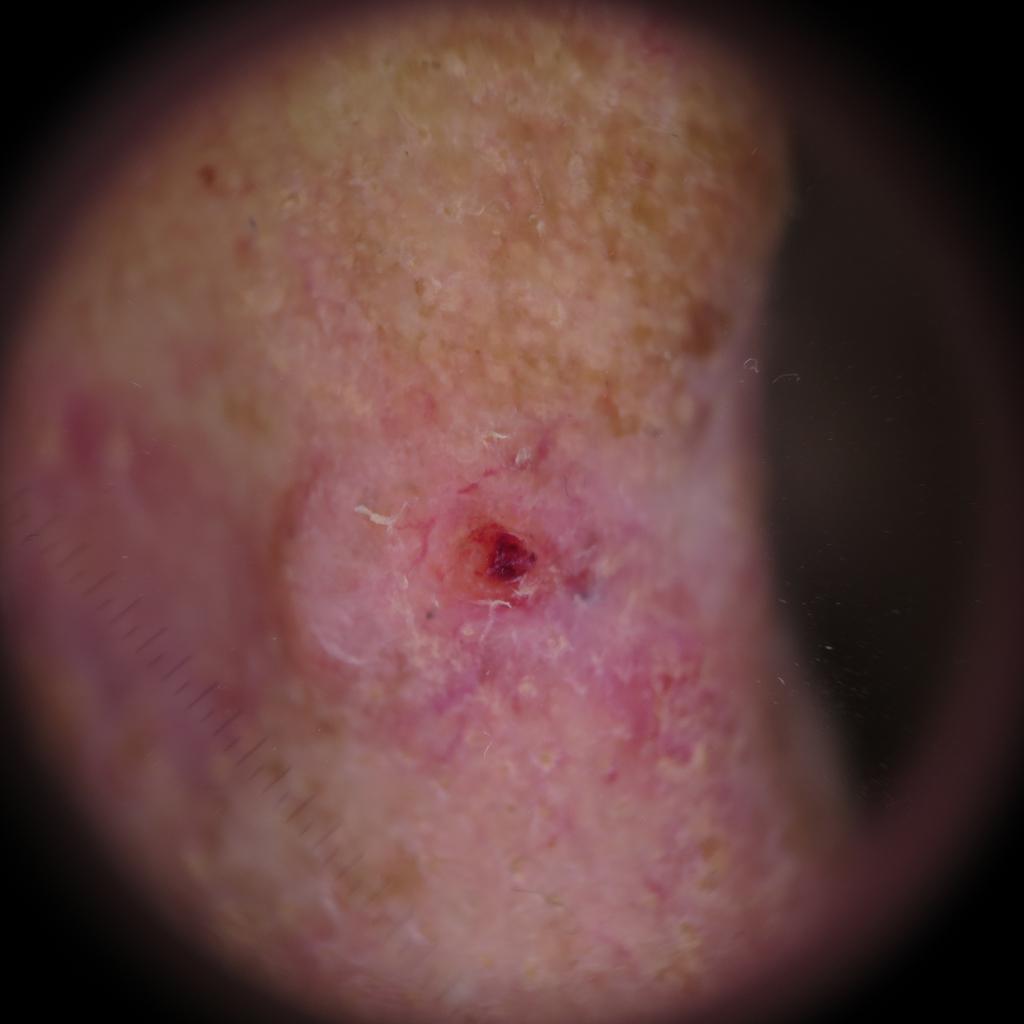

Basal cell carcinoma presenting as an open sore on the ear. Photo: International Skin Imaging Collaboration at isic-archive.com

A small pink growth with a slightly raised, rolled edge and a crusted indentation in the center. (BCC)